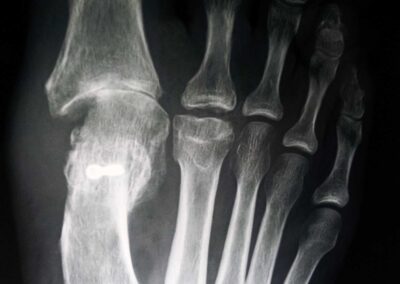

Alluce valgo

E’ frequente specie nelle donne e prevede, quando indicato, un trattamento chirurgico. E’ importante considerare univocamente anche le patologie eventualmente associate dell’avampiede e del retropiede per una corretta indicazione chirurgica. Lo studio clinico poi deve essere integrato da una radiografia dei piedi in comparativa e sotto carico gravitario.

Il problema della chirurgia riparativa dell’ alluce valgo è la recidiva della deformità che addirittura è meno grave della ipercorrezione con conseguente alluce varo secondario. Occorre dunque programmare le osteotomie eventualmente associate alla testa del primo metatarso ed alla base della prima falange con un accurato planning preoperatorio in base a parametri morfologici da ricercare in una radiografia preoperatoria eseguita sotto carico gravitario.E’ fondamentale associare un riequilibrio delle parti molli capsulari e tendinee che andranno opportunemente adattate alla nuova configurazione geometrica dell’avampiede.Sarà poi importante l’ausilio di bendaggi o taping nelle prime settimane postoperatorie a mantenere la correzione ottenuta fino alla completa guarigione delle correzioni ossee e delle parti molli.Preciso che è fondamentale seguire l’evoluzione della cicatrizzazione con controlli ogni due settimane nei primi 45gg postoperatori con possibilità di correggere con adeguati taping eventuali iper piuttosto che ipo correzioni.